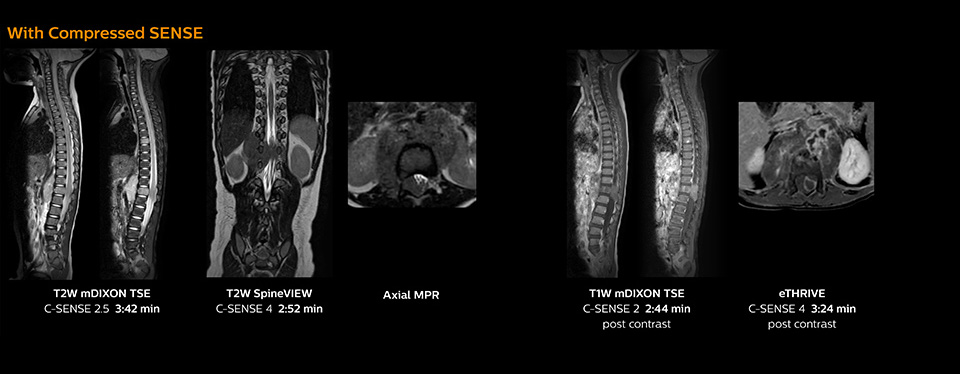

“Previously with SENSE, our 2D mDIXON TSE scans required relatively long scan times. But now, with Compressed SENSE, we have reduced these scan times while maintaining a high SNR, because the Compressed SENSE technology helps reduce noise,” says Dr. Koyama. “Because the faster scanning with Compressed SENSE saves us time, we can sometimes add a sequence to obtain high quality spine images in the same time slot for confident diagnoses. And in cervical spine exams, a 2D sequence is sometimes replaced by a 3D protocol, which provides us more information as it can be reformatted in different orientations. Compressed SENSE allows us to easily add this 3D sequence in the timeslot,” says Fukushima “Incorporating Compressed SENSE in common spine sequences, such as mDIXON, 3D SpineVIEW and eTHRIVE, can substantially reduce the scanning time of these sequences, while maintaining adequate spatial resolution, resulting in high quality, multiple contrasts, multiple orientations,” says Dr. Koyama. “In addition, fast sequences generally make it easier for patients to stay motionless throughout the scans, so it also helps us in that way.”

The KCH team has already changed most of their Ingenia 1.5T spine ExamCards by incorporating Compressed SENSE into their 2D TSE, mDIXON TSE, FFE, and 3D sequences.

This 6-year-old patient with neuroblastoma underwent MRI on the Ingenia 1.5T. Compressed SENSE was used to reduce scan time while maintaining the high resolution for 2D mDIXON, 3D SpineVIEW and e-THRIVE in this case. The highly detailed images allowed the radiologist to make a quick and confident assessment of the position of the nerve and the tumor. Especially important for a pediatric patient, is that a shorter scan time also allows us to keep the sedation time as short as possible.

As this was one of the first patients scanned with Compressed SENSE, 3D SpineVIEW was acquired with and without Compressed SENSE to allow comparison. Although the Compressed SENSE sequence was significantly faster, the acquired and reconstructed 3D SpineVIEW images show virtually the same image quality.